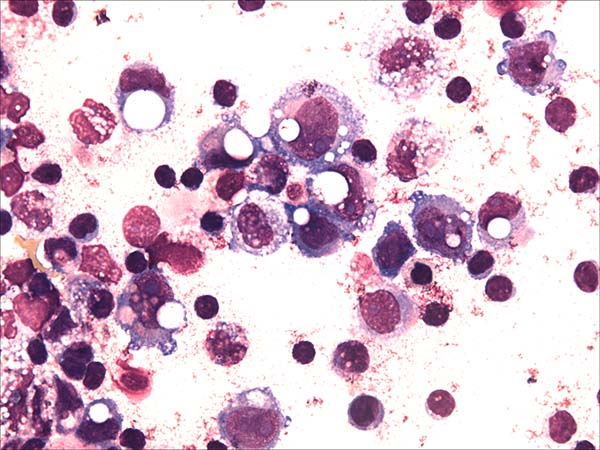

A 52-year-old woman with a history of breast cancer presented with left breast swelling and local pain. Seven years before, she had undergone a modified radical mastectomy of her left breast and had thereafter undergone immediate breast reconstruction with tissue expander. She had then developed a surgical infection, and shortly thereafter had the expander removed. Six months after completing radiotherapy, she had undergone another breast reconstruction using a latissimus dorsi flap and textured anatomical-shaped implant. Upon presentation, imaging revealed a peri-implant effusion. Approximately 100 ml of cloudy, yellow fluid was collected and immediately sent to the flow cytometry lab. Cytological examination revealed numerous large, anaplastic cells with pleomorphic nuclei, prominent nucleoli, and moderate basophilic cytoplasm with frequent vacuoles (Figure 1). Multiparametric flow cytometry (MFC) immunophenotyping revealed large tumor cells (increased FSC/SSC scatter) with bright expression of CD30, CD45, CD25 and HLA-DR, as well as the absence of CD3 expression within T-lineage cells and a lack of the B-cell antigens CD19 and CD20 (Figure 2). The patient underwent a bilateral breast implant removal and a total capsulectomy. Pathological examination of the seroma then confirmed the presence of clustered large lymphoma cells that were immunohistochemically positive for CD30 and negative for CD20 and CD3 (Figure 3). However, histologic sections of the breast capsule showed only fibrin admixed with infiltrating reactive lymph histiocytes.